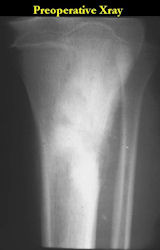

Radiographic Presentation: Conventional Osteosarcoma

There are 3 radiographic presentations for osteosarcomas, depending upon the amount of osteoid/ossification and calcium deposition:

- Mixed sclerotic and lytic, permeative lesion most common radiographic presentation

- Purely osteoblastic, permeative lesion: dense sclerosis and osteoid production

- Purely lytic, permeative lesion: little osteoid production and/or minimal calcium deposition in osteoid

Conventional osteosarcomas are permeative lesions on plain radiographs (borders of the lesion cannot be clearly delineated)

- Wide zone of transition from lytic/sclerotic areas of tumor to normal bone

- Makes borders of lesion hard to define

- Most (90%) arise from the metaphysis of the bone

- Rarely (10%) arise from the diaphysis

- Most conventional osteosarcomas (90-95%) extend through the bone into the soft tissues and form a soft tissue mass outside of the bone